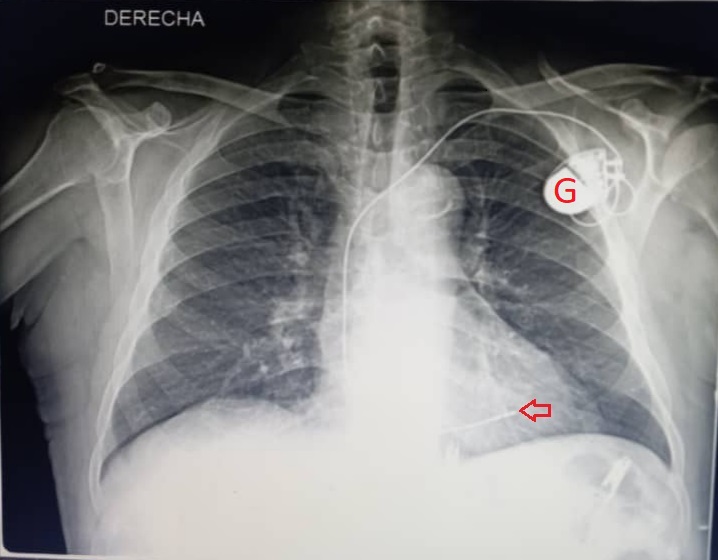

Se trasladó el paciente a la sala, y se le realizó radiografía posteroanterior de tórax para comprobar que la posición anatómica del marcapasos fuese correcta, y descartar que hubiese complicaciones pleuropulmonares (Fig. 2).

Fig. 2 - Radiografía posteroanterior de tórax. Obsérvense el generador (G roja), y el electrodo insertado en el ápex ventricular derecho (flecha roja).